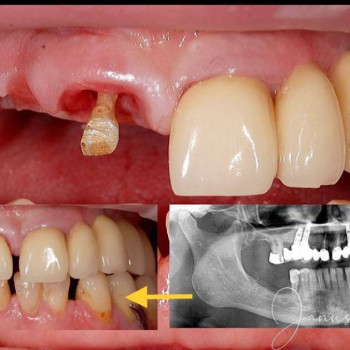

| Installation von Zahnkronen | |

| Installation von Zahnkronen aus Keramik | |

| Zahnbrückenverfahren | |

| Zahnimplantation in einem Schritt | |

| Einzeitige Zahnimplantatchirurgie | |